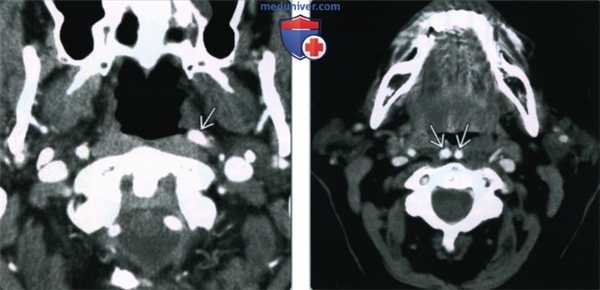

2. КТ при извитости сонной артерии:

• КТ с КУ:

о Сосудокруглой (аксиальная проекция) или цилиндрической (коронарная проекция) формы

о Непрерывный ход артерии определяется при последовательном анализе аксиальных срезов

о Изменены могут быть как одна, так и две артерии:

- Извитость обеих сонных артерий = «целующиеся» сонные артерии

• КТ-ангиография:

о Лучше всего извитость сонной артерии визуализируется на коронарных срезах

о Чаще всего извитым оказывается дистальный сегмент общей сонной артерии + проксимальный сегмент внутренней сонной артерии